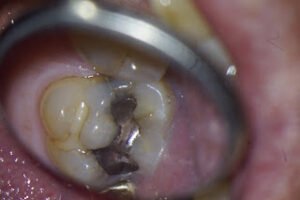

This patient was mostly asymptomatic until he recently bit into something and has had pain ever since.

2 Cracks seen on the MMR – with staining